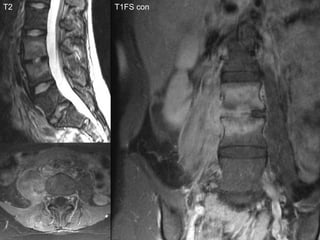

T2 T1 T1FS con

T2 T1FS con

•  62 year old male

•  Severe low back pain of rapid onset

•  Febrile and unwell

•  4 weeks ago underwent abdominal

surgery for perforated diverticulitis

MRI